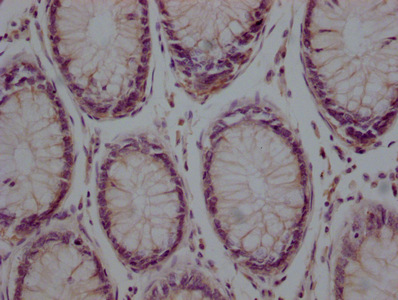

靶點(diǎn)檢測(cè)是一種通過(guò)尋找特定分子或細(xì)胞上的目標(biāo)結(jié)構(gòu)來(lái)確定靶點(diǎn)的方法,用于癌癥治療的靶向藥物研發(fā)中非常重要。以下是一些常用的方法來(lái)